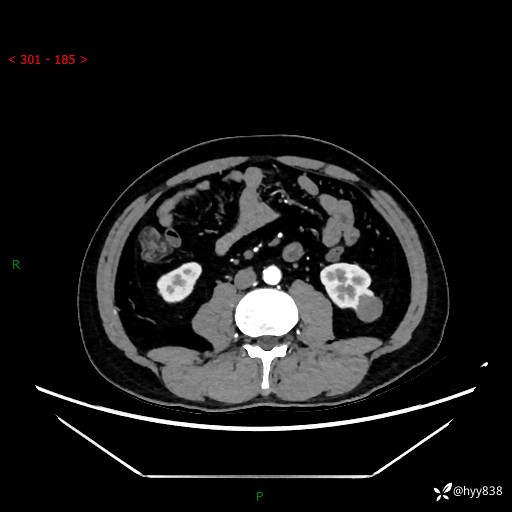

中年男性,左侧腰背部间断性胀痛不适。第一眼“乳头或囊肿”,有无意外---(有结果)

【患者信息】:41岁/男

【主诉】:左侧腰背部间断性胀痛不适1周

【现病史及既往史】:患者1周前无明显诱因出现左侧腰部疼痛,呈间断性胀痛,休息后可缓解,无放射痛,偶可见肉眼血尿,无血块,无尿频尿急尿痛,无夜尿增多,无畏寒发热、咳嗽咳痰等症状。于我院查双肾CT示:左肾占位性病变,左肾下极囊性病变,左肾轻度积水,胆囊多发结石。今为求进一步诊治来我院,门诊以“左肾占位性病变”收治入院。 起病以来,患者精神佳,饮食、睡眠良好,大便正常,小便如上诉,体力体重无明显变化。

【检查】:肾脏CT平扫+增强